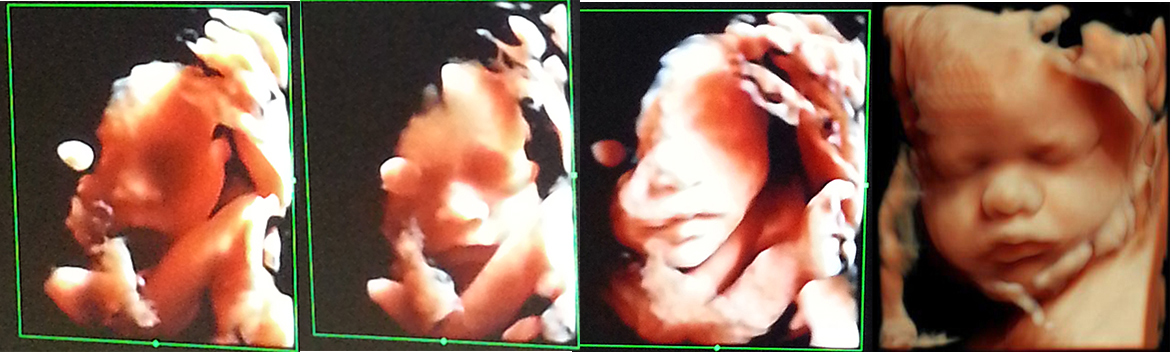

1、图像更清晰生动,更具真实感: GE四维彩照拍摄的图像不仅不其他四维彩超的图像更加清晰和准确,图像也更有真实感,并且其还能实现动态抓拍,能生动形象的看到宝宝的各种动作。